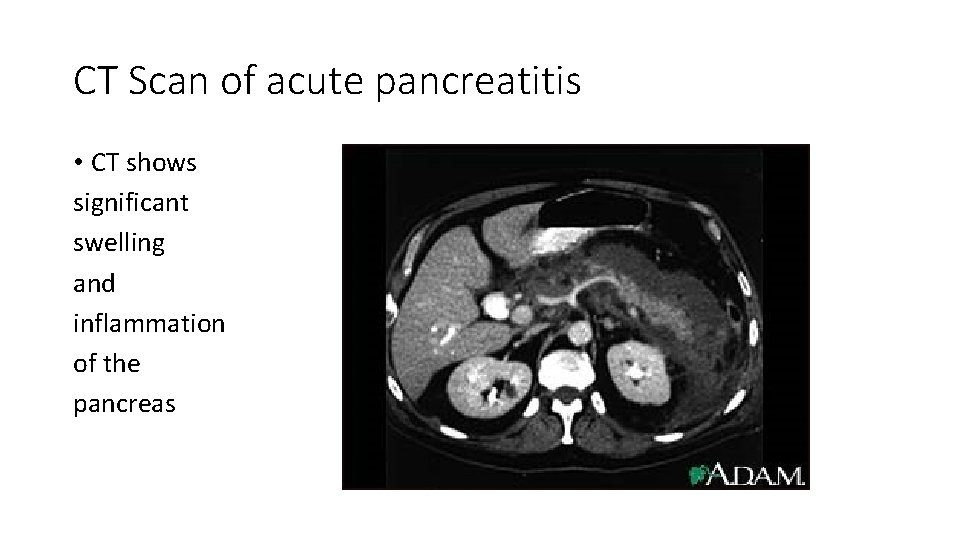

CT Findings and Grading of Acute Pancreatitis [CT Severity Index (Ctsi)] Grade Findings Score A 0 Normal pancreas: normal size, sharply defined, smooth contour, homogeneous enhancement, retroperitoneal peripancreatic fat without enhancement B Focal or diffuse enlargement of the pancreas, contour may show irregularity, enhancement may be inhomogeneous but there is no peripancreatic 1 inflammation C Peripancreatic inflammation with intrinsic pancreatic abnormalities 2 D Intrapancreatic or extrapancreatic fluid collections 3 E Two or more large collections or gas in the pancreas or retroperitoneum 4

Necrosis score based on contrast-enhanced CT Necrosis (%) Score 0 0 <33% 2 33 -50% 4 >50% 6 CT severity index equals unenhanced CT score plus necrosis score; 6 = severe disease.

CT Scan of acute pancreatitis • CT shows significant swelling and inflammation of the pancreas